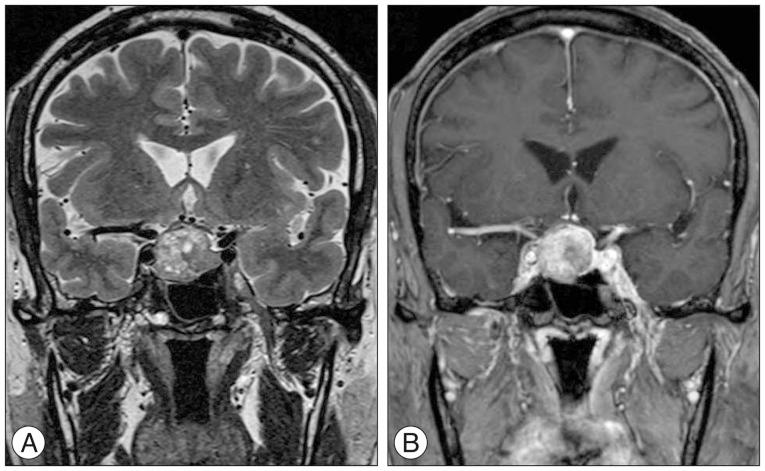

From November 2008 to August 2015, of the 286 patients who underwent EETS by the senior author, 208 were pituitary adenoma cases (146 non-functioning pituitary adenomas, 10 adrenocorticotropic hormone-secreting adenomas, 31 growth hormone-secreting adenomas, 17 prolactin-secreting adenomas, and 4 thyroid-stimulating hormone-secreting adenomas; 23 microadenomas, 174 macroadenomas, and 11 giant adenomas). Two neurosurgeons and a neuroradiologist independently measured the degree of parasellar extension on the preoperative sellar MRI according to the modified Knosp's classification. Inter-rater reliability was statistically assessed by measuring the intraclass correlation coefficient. The extents of resection were evaluated by comparison of the pre- and post-operative MR images; the neurovascular complications were assessed by reviewing the patients' medical records. The extent of resection was measured in each parasellar extension grade; thereafter, their statistical differences were calculated.

2008年11月至2015年8月,由资深作者实施EETS的286例患者中,208例为垂体腺瘤病例(146例无功能垂体腺瘤、10例促肾上腺皮质激素分泌腺瘤、31例生长激素分泌腺瘤、17例催乳素分泌腺瘤和4例促甲状腺激素分泌腺瘤;23例微腺瘤、174例大腺瘤和11例巨大腺瘤)。两名神经外科医生和一名神经放射科医生根据改良的Knosp分类法,在术前蝶鞍MRI上独立测量鞍旁扩展程度。通过测量组内相关系数对评分者间信度进行统计学评估。通过比较术前和术后的MR图像评估切除范围;通过查阅患者病历评估神经血管并发症。测量每个鞍旁扩展分级的切除范围;之后计算它们的统计学差异。